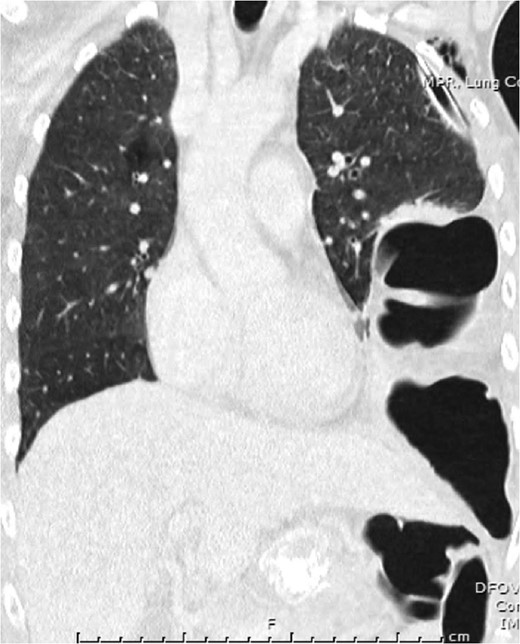

Reduction of transverse colon into abdominal cavity. The spleen is visible adjacent to the transverse colon. Black asterisk (*) indicates a loop of transverse colon. Blue broken arrow indicates the diaphragmatic defect that was extended to successfully reduce the colon.